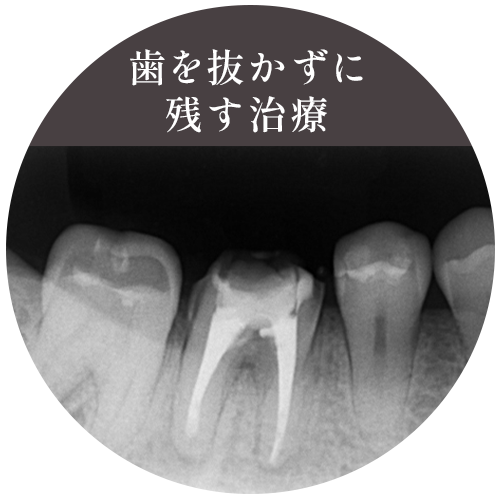

歯を抜かずに残す治療

できる限り「抜歯しない」

歯の根に炎症が起こり膿が溜まると、通常の根管治療では治療が難しい場合があります。さらに、神経を失った歯は薄く脆くなりヒビが入ったり割れてしまうこともあります。このような場合、多くの歯科医院では「抜歯」を選択します。しかし、抜歯をせずに治療が可能な場合もあります。当院では、精度の高い根管治療や、外科的に膿を取り除く治療法など、なるべく抜歯せずに歯を残すことを目指しています。